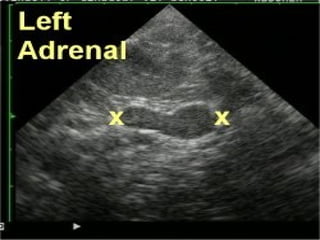

Glándula suprarrenal

Compuesta por: Corteza         Médula

Peso: 7 a 12 gr.                Medida: 2.5 a 3 cm.

Ubicación: Antero interna y superior con respecto al riñón en el interior de la fascia

de Gerota.

EVALUACIÓN ECOGRÁFICA

La evaluación de las glándulas adrenales

consiste en describir:

La posición,

La forma,

La ecogenicidad,

La arquitectura y

El tamaño de cada glándula adrenal.